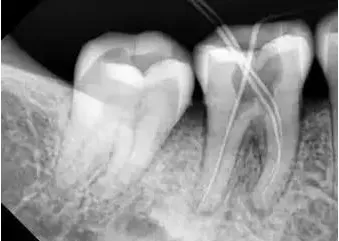

根管治疗作为口腔科最基础的治疗方法,可以缓解因为牙髓炎而导致的剧烈牙痛,操作过程中表面上看只是补了一个牙,实际上牙医做的事情远比补牙复杂!

今天,我们就来聊聊根管治疗中让人“嘶~哈”不已的“断针”到底是怎么回事?

一、为什么会出现断针的情况?